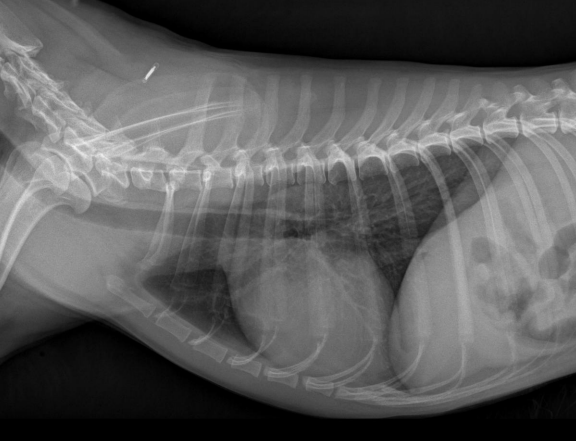

Radiografia laterolateral

Dependiendo de la posición los gases van a un lado o a otro: Decúbito lateral derecho Radiografía Lateral

- Gas en fundus

- Se ve mejor cola del bazo

- Mayor separación de siluetas renales

Decúbito lateral izquierdo

- Gas en píloro

- Mejor visualización delduodeno

Radiografia ventrodorsal

La vertebra L2 tiene que caber entre 2,5 veces y 3,5 veces en el perro, entre 2,4 y 3 en el gato